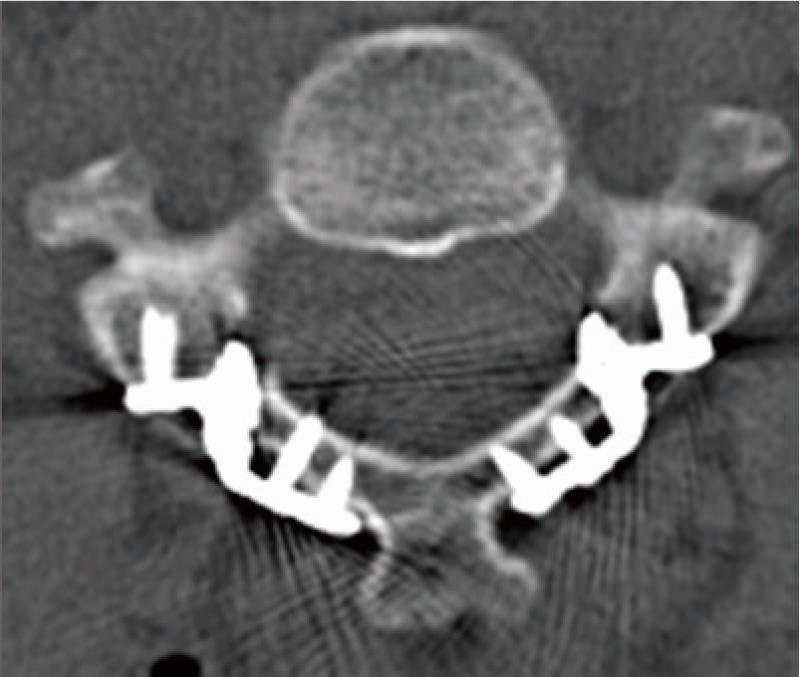

病例4: 颈椎骨性斜颈矫形术

骨性斜颈,术前X线和CT示颈椎半椎体合并椎体分隔不全畸形

颈椎前路后路联合截骨矫形术,随访X线和CT示矫形效果满意。